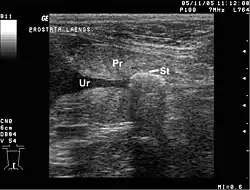

Ultraschallbild eines Harnsteins im Prostatateil der Harnröhre beim männlichen Hund. (Ur=Urethra (Harnröhre), Pr=Prostata, St= Harnstein)

Verletzungen der Harnröhre werden in „hintere“ und „vordere“ Harnröhrenverletzungen eingeteilt, die sich hinsichtlich ihrer Ursache unterscheiden. Mit hinteren Harnröhrenverletzungen sind Verletzungen der Harnröhre oberhalb ihres Durchtritts durch den Beckenboden gemeint. Sie entstehen meistens bei Beckenbrüchen durch massive Gewalteinwirkung, also bei Verkehrsunfällen und Stürzen aus großer Höhe. Harnröhren von Männern sind häufiger davon betroffen als die Harnröhren von Frauen. Vordere Harnröhrenverletzungen sind Verletzungen der Harnröhre unterhalb des Beckenbodens. Bei Erwachsenen sind ärztliche Maßnahmen als Ursachen führend, also das Einführen von Instrumenten und das Legen und zu lange Liegen von Blasenkathetern. Auch hier sind männliche Harnröhren häufiger betroffen, insbesondere zu lange liegende Katheter können zu Strikturen des Penisteils der Harnröhre führen. Verletzungen durch andere eingeführte Gegenstände, etwa zur sexuellen Stimulation, sind selten und betreffen die Harnröhre nah an ihrer Öffnung. Bei Kindern treten traumatisch bedingte vordere Harnröhrenverletzungen häufiger auf als bei Erwachsenen, vor allem durch Anpralltraumen gegen das Perineum. Bei Männern, die eine Penisruptur erleiden, ist in 20 % der Fälle auch die Harnröhre betroffen.[48]

Auch Harnsteine (Urolithiasis), die aus der Harnblase in die Harnröhre geschwemmt werden oder erst in der Harnröhre entstehen, kommen vor und können zu einer Verengung oder Striktur führen.[27] Dabei handelt es sich um krankhafte feste Gebilde (Konkremente), die sich aus Mineralsalzen im Urin bilden können. Sie heißen korrekt Urethralith[49] oder falsch Urethrolith;[50] das Reallexikon der Medizin nennt nur Urethralstein und Urethrastein.[51]